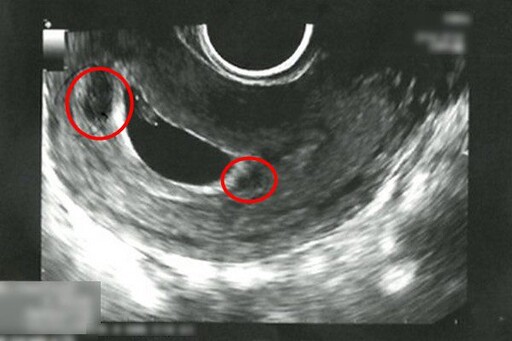

▲陳女士懷孕第六週,透過超音波檢查發現子宮腔內出現血塊(紅圈處)。

▲經過一週的中醫住院治療,子宮腔內血塊已消失,且胎兒順利成長。